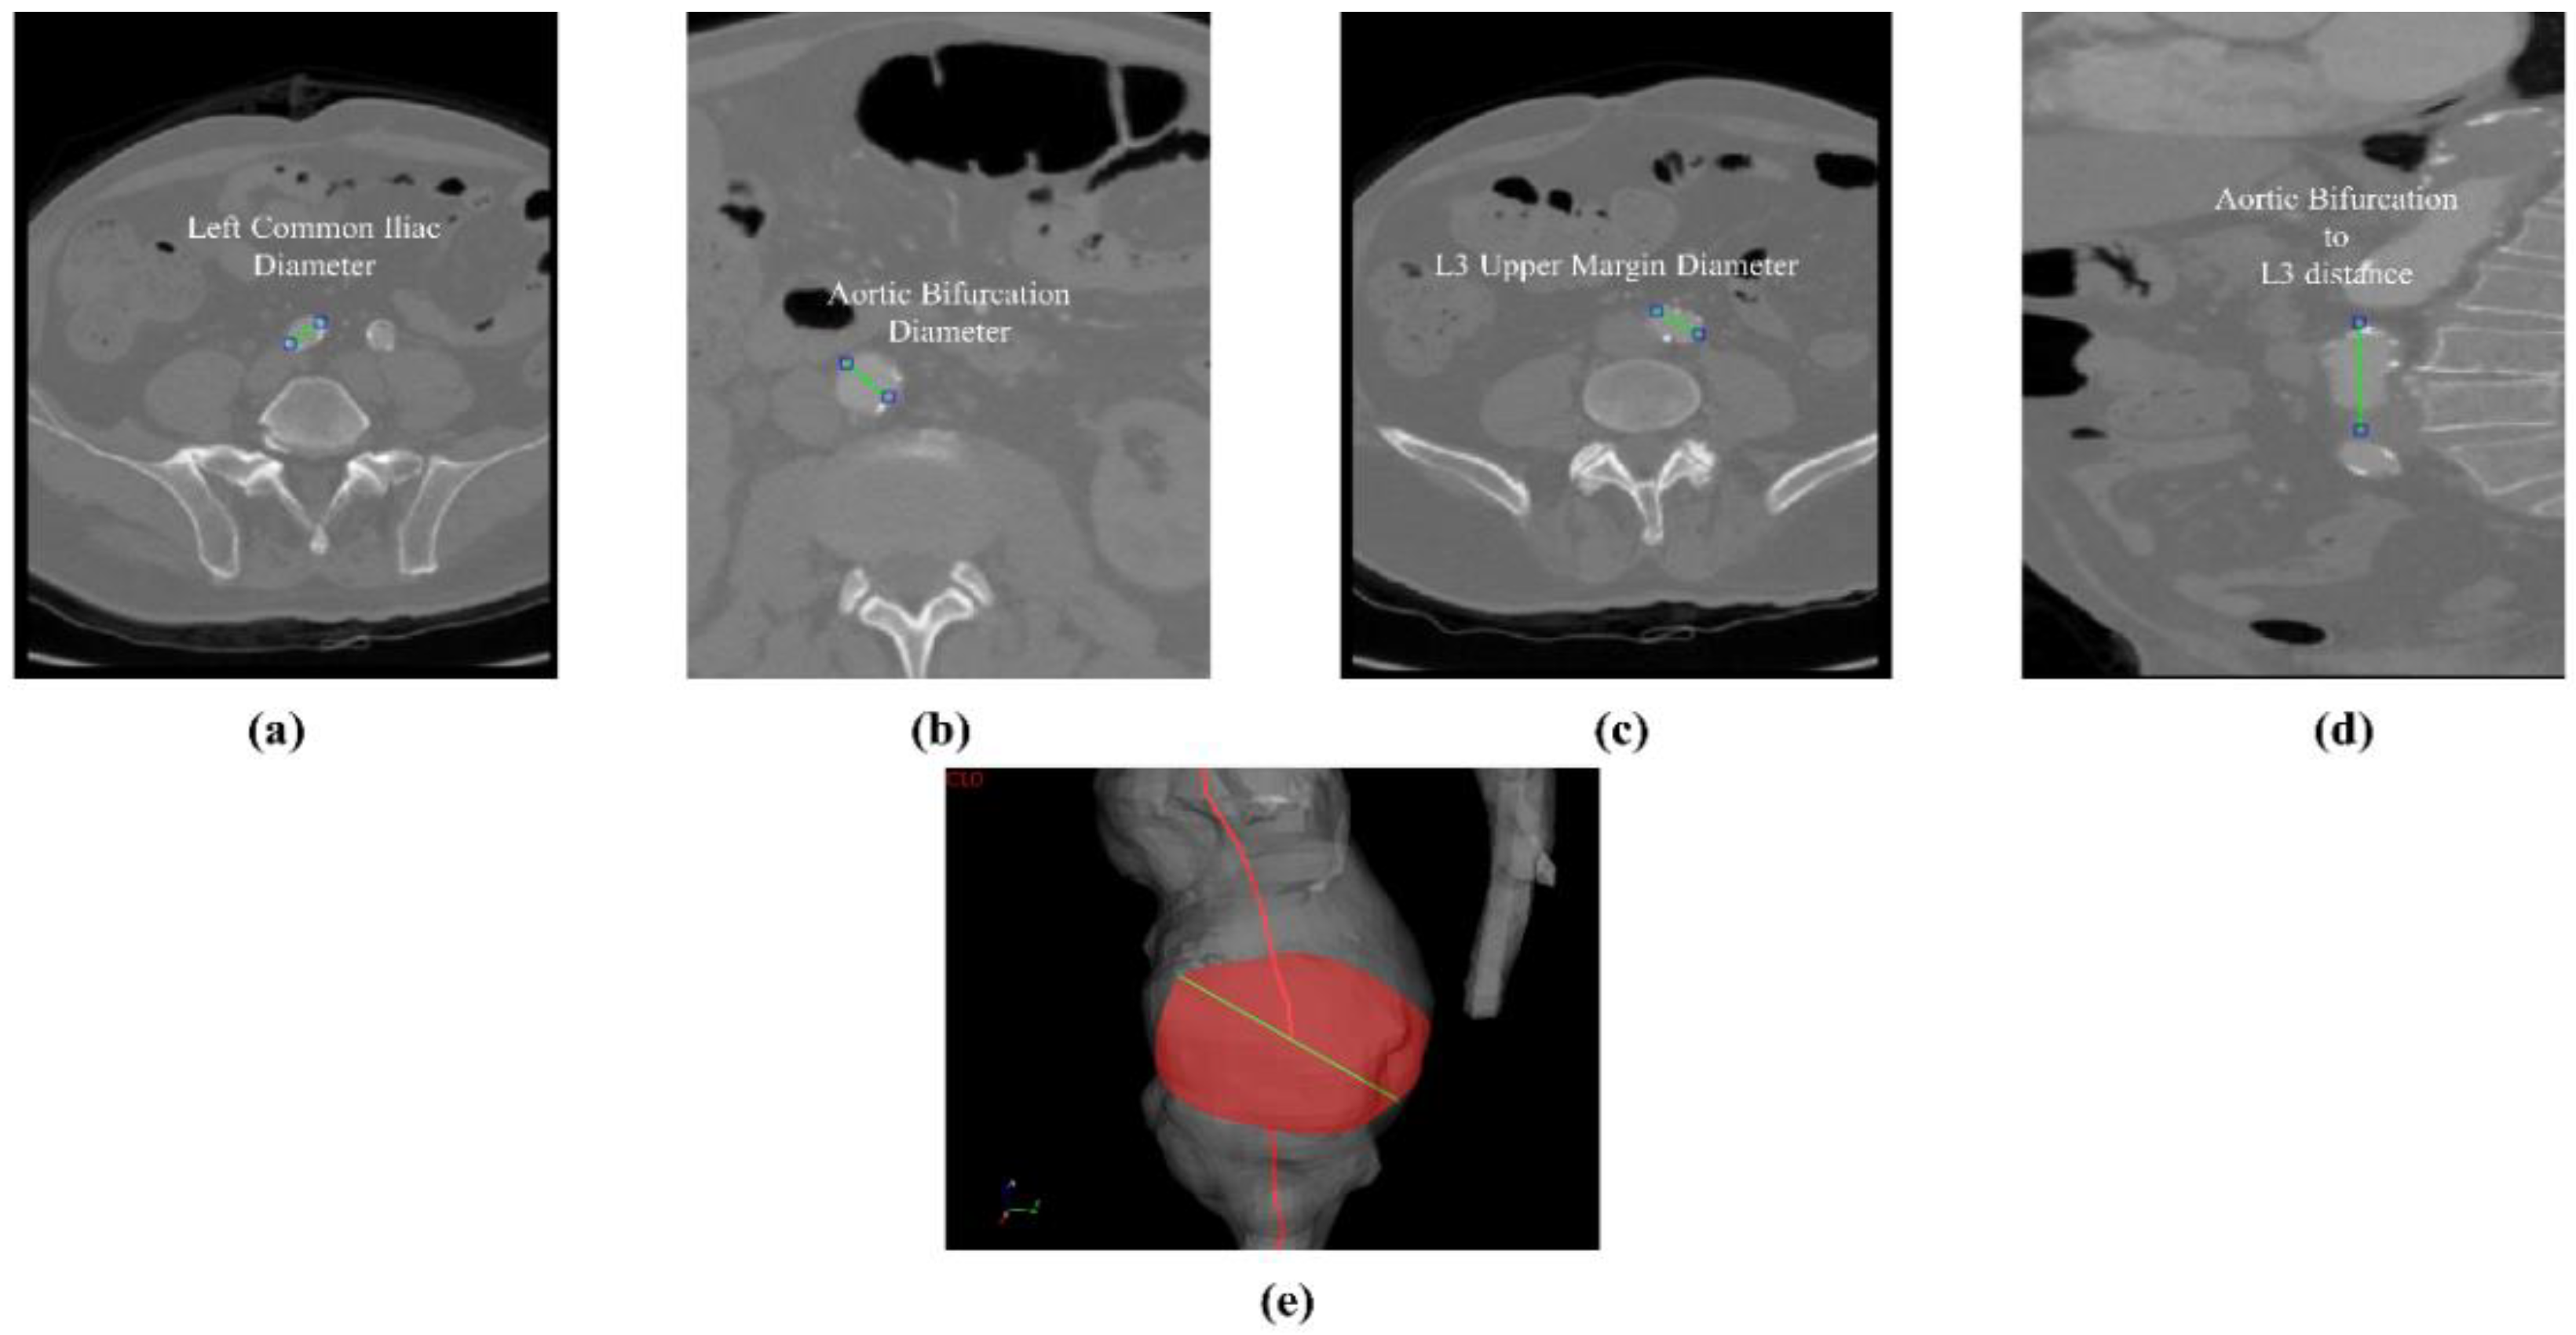

where v G T and v m are the diameter or centerline length values, respectively, measured on ITK-Snap and U-Net 3D reconstruction geometries. Bland–Altman plots are also provided in the Appendix section from Figure A1, Figure A2, Figure A3 and Figure A4 for diameters and from Figure A5, Figure A6 and Figure A7 for the centerline’s length. Once a region of interest is reconstructed, the vessel’s centerline is computed. The user can then perform the required reference measurements, taken on a plane orthogonal to the centerline, as shown in Figure 4e. The abdominal aneurysm and iliac arteries’ lumen diameter are measured at three distinct locations:

• Right/Left Iliac Luminal Diameter, ϕ r , i l i a c , ϕ l , i l i a c : right and left common iliac artery proximally to their bifurcation, as shown in Figure 4a.

• L3 Infra Renal Aortic Diameter, ϕ L 3 : located on the third lumbar vertebral body’s upper margin (L3), as shown in Figure 4b, and at a distance l A B L 3 from AB, as shown in Figure 4d.

• Juxta Renal Aortic Diameter, ϕ j u x t r : the aortic lumen immediately below the lowest renal artery, as shown in Figure 4c.

The coronal plane was used to measure the vertical distance between the aortic bifurcation and L3 body l A B L 3 , as shown in Figure 4d. The centerline-based aortic lumen’s length measure between reference sections is taken considering the following bound segments:

Figure 4. Intraluminal diameter obtained at different segments on the axial plane (cm). Left common iliac, (a) aortic bifurcation, (b) aortic diameter at the L3’s upper margin, (c) l A B L 3 distance from the upper margin of L3 body to the aortic bifurcation, (d) visual, manually measured centerline-based diameter visual sample in GUI (e).